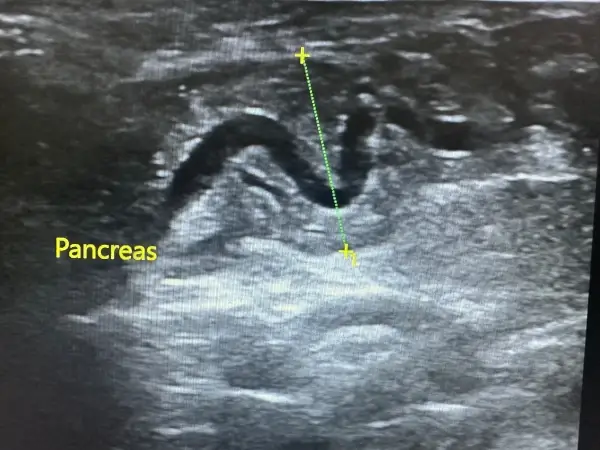

Ecografía abdominal y cardíaca: La ecografía es una técnica no invasiva que permite visualizar órganos internos en tiempo real, evaluando su estructura, tamaño y vascularización. A diferencia de la radiografía, no utiliza radiación y proporciona información sobre la arquitectura interna de los órganos.

Nuestro ecógrafo de alta gama con tecnología doppler color permite:

- Evaluación detallada de riñones, hígado, bazo, páncreas e intestino

- Diagnóstico de masas abdominales y diferenciación de su naturaleza

- Valoración de la vejiga y detección de cálculos urinarios

- Ecocardiografía para diagnóstico de cardiomiopatías

- Medición de flujos sanguíneos y evaluación de función valvular

La ecografía abdominal es especialmente útil en el diagnóstico de enfermedad renal crónica, permitiendo evaluar el tamaño, la ecogenicidad y la arquitectura renal. Podemos detectar quistes, cálculos renales, hidronefrosis y cambios estructurales indicativos de daño renal antes de que aparezcan síntomas clínicos.

La ecocardiografía es el gold standard para el diagnóstico de cardiomiopatía hipertrófica, la enfermedad cardíaca más frecuente en gatos. Permite medir el grosor de las paredes ventriculares, evaluar la función sistólica y diastólica y detectar trombos intracardíacos que pueden causar embolismo arterial.

Contamos con ecografía abdominal, análisis específicos y pruebas complementarias que nos permiten llegar a la causa del problema de manera rápida y precisa.